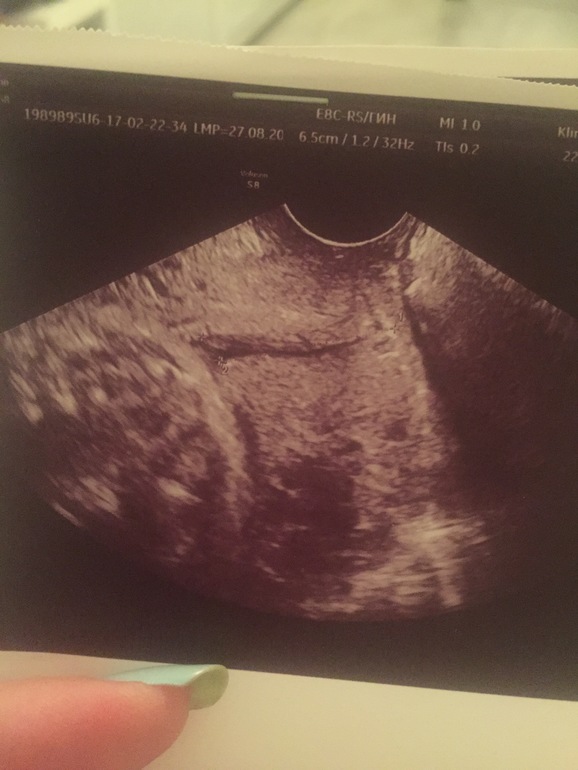

Если кто-то понимает в фото узи шейки матки, то расшифруйте, пжл, где тут что:

А вы можете подсказать, о чем говорит расстояние между крестиками? Их ж 4. И где внутренний и внешний зев? Я как только не кручу, не понимаю.

Расстояние между крестик аминь это и есть длина которую отметили. А то что 4 крестика, то по моему тут на снимке сразу два среза вместе

Спасибо большое! А что означает расстояние между двумя другими крестиками?